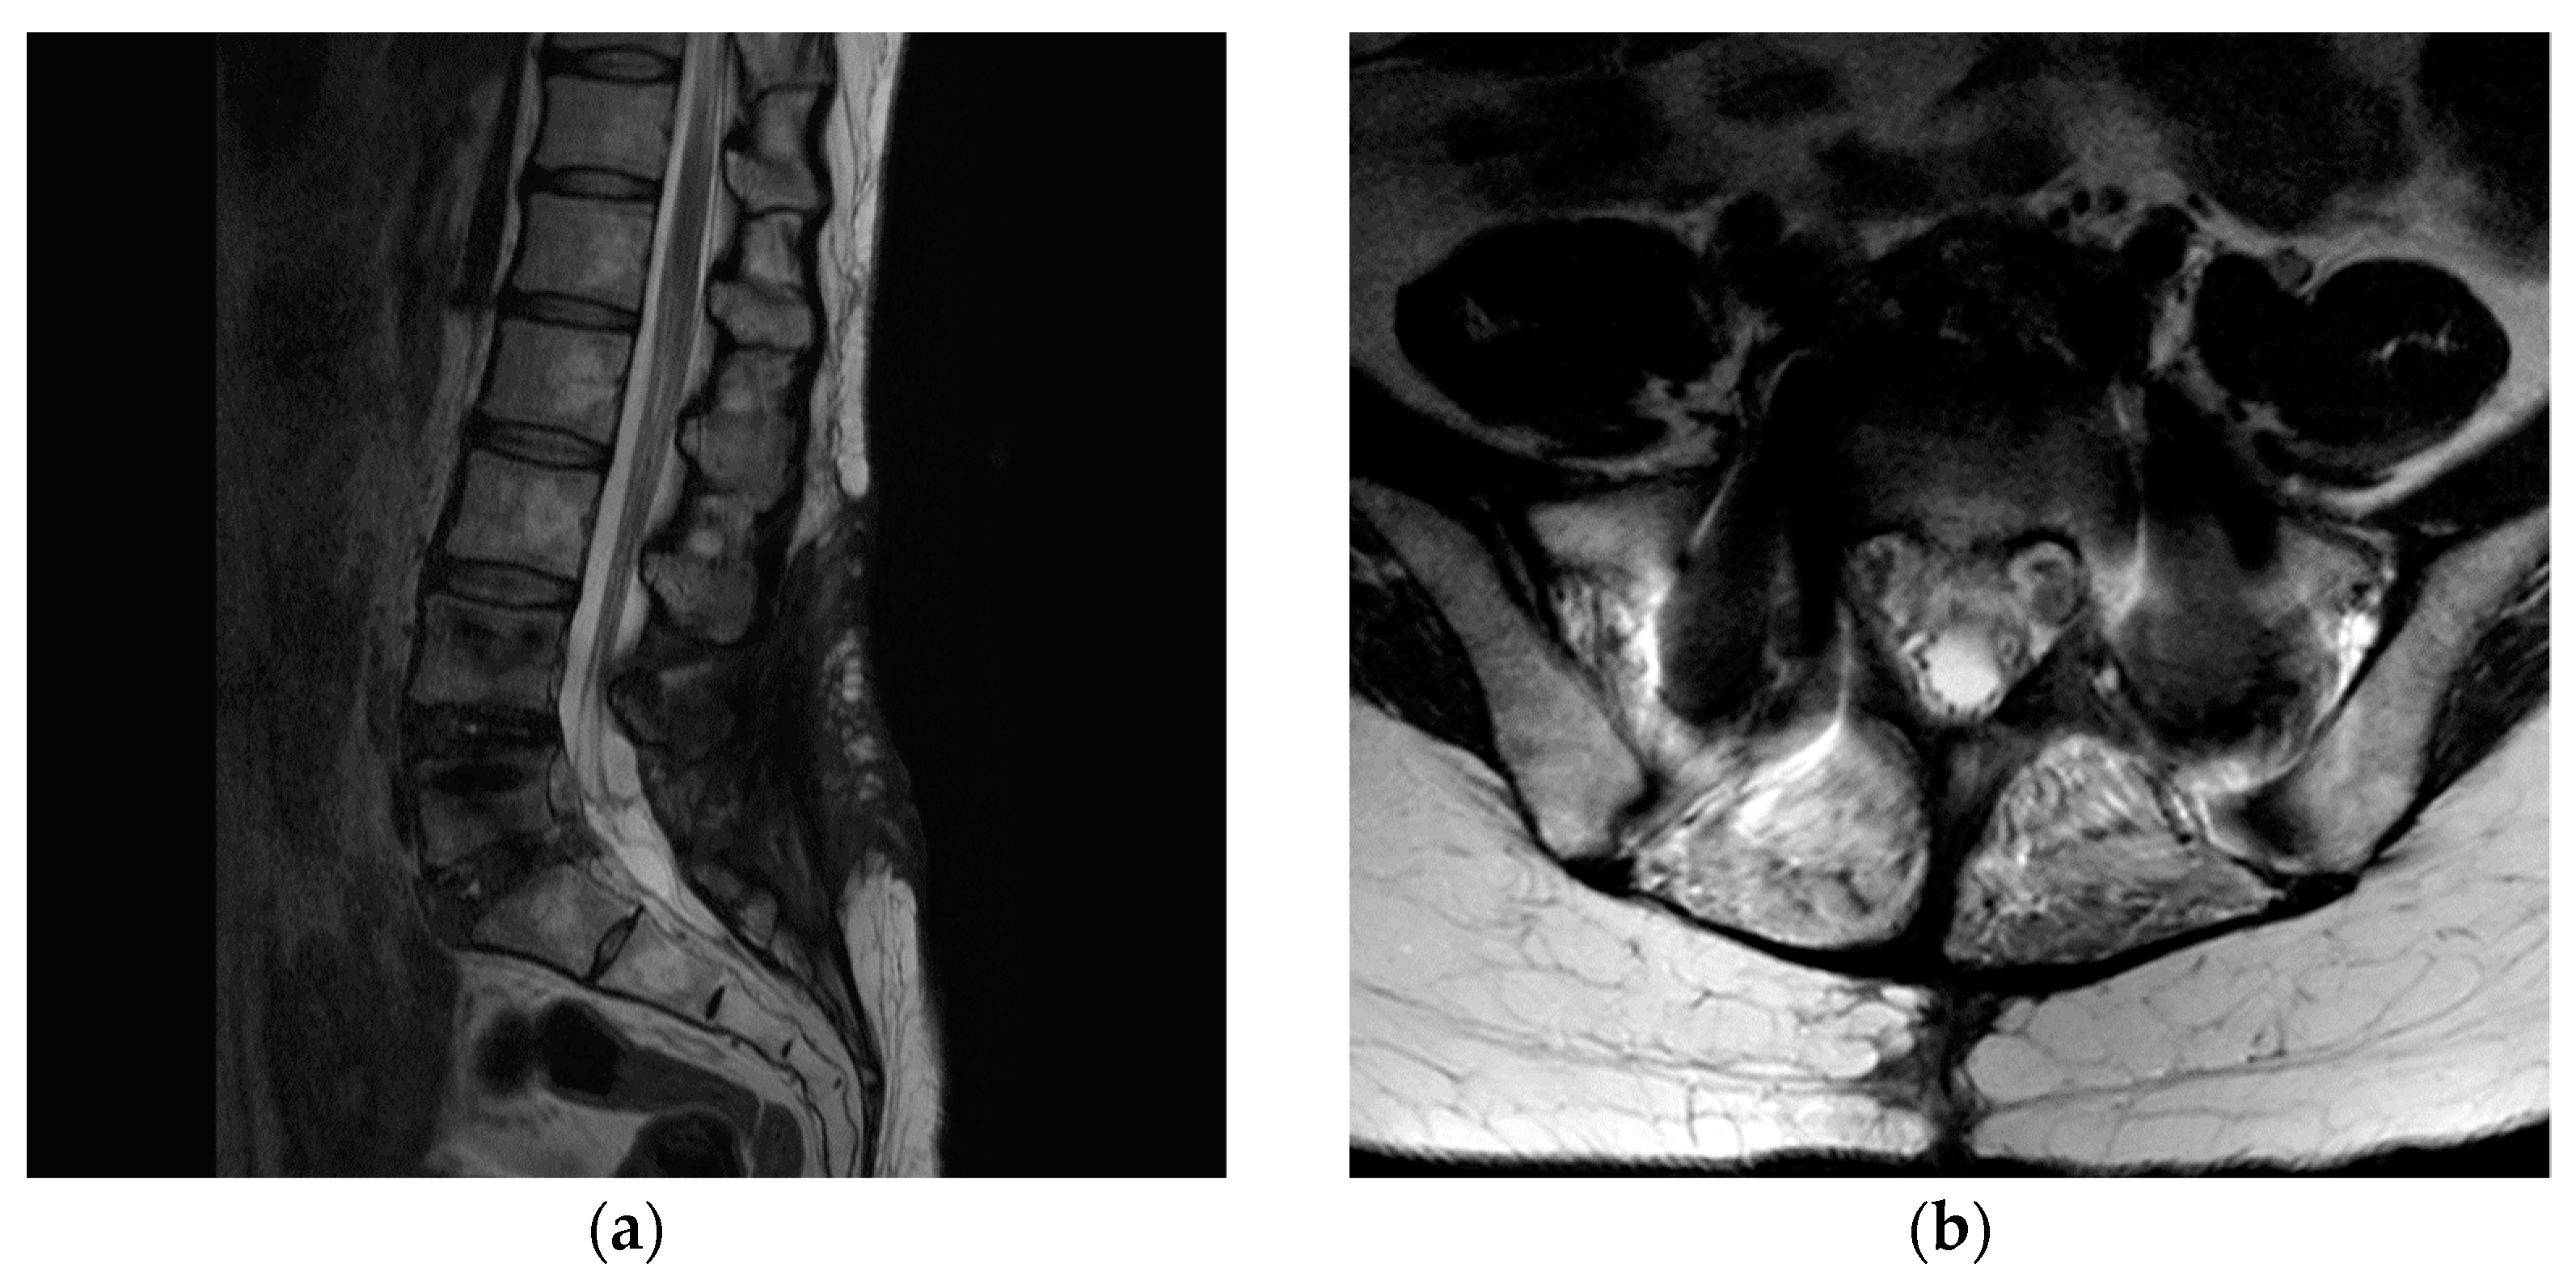

Five days after surgery, she complained of severe pain in her left lower extremity again. Following wound exploration with additional laminectomy, revealing no significant compressive lesion except epidural fibrosis, the symptom improved. Six days after revision surgery, she complained of gradually increasing pain in her left lower extremity, followed by profound weakness (no voluntary movement in the left ankle and big toe dorsiflexion and ankle plantarflexion). Revision surgery revealed severe epidural fibrosis along the thecal sac and L5–S1 roots (left side dominant). Normal dura was identified after peeling the thick epidural fibrosis (Figure 3). Pain and weakness of the left extremity disappeared immediately after surgery. However, two additional surgeries were needed due to the same pain and weakness episodes, several days following the surgeries. Operative findings were also similar to that of the previous surgeries with severe epidural fibrosis around the thecal sac and nerve roots. Symptoms were also alleviated immediately after surgery. Postoperative steroid therapy or narcotics did not work at all. Laboratory and culture studies documented no evidence of infection or rheumatoid disease. Finally, we performed L4–S1 oblique lateral interbody fusion (OLIF) with hyperlordotic cages to ameliorate tethering and traction of the thecal sac and nerve roots through posterior column shortening (Figure 4). Pain and paresthesia were considerably decreased. Weakness was also reduced. Eventually, the patient was able to walk again following six additional surgeries over 11 weeks. After the final surgery, postoperative wound infection by Candida albicans was identified, and treated successfully with antifungal agents. Follow-up MRI at 6 months postoperatively showed a well-decompressed thecal sac and nerve roots. However, roots were clumped and distorted within the thecal sac, suggesting arachnoiditis (Figure 5). Fortunately, her pain in the leg was considerably reduced, without neurological deficits. At the final follow-up, she was doing well with oral medication without taking narcotics (VAS 3) over the 2 years postoperatively.

Figure 5.

(a,b) Magnetic resonance imaging at 6 months postoperatively showed a well-decompressed thecal sac and nerve roots. However, roots were clumped and distorted within the thecal sac, suggesting arachnoiditis.